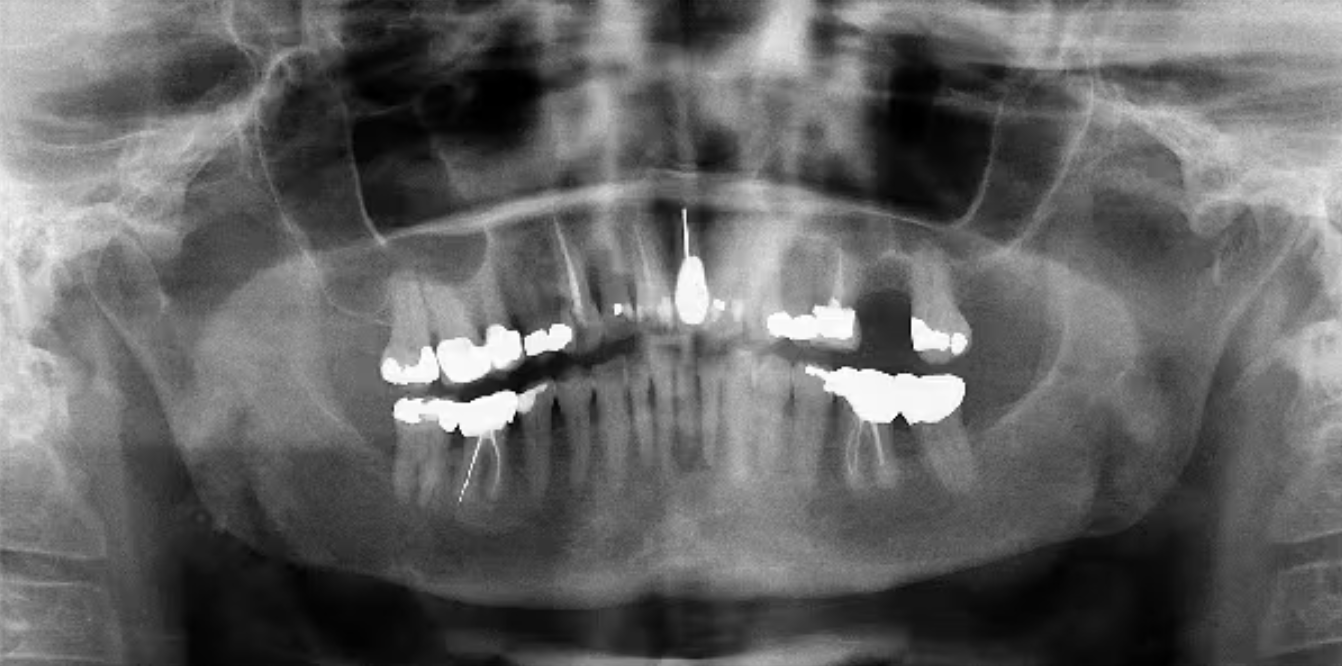

Hình ảnh X-quang Panorex: vùng thấu quang 2–3 cm, bờ mờ, nằm ở thân sau và ngành lên hàm dưới, lan đến răng số 31.

2. Hình ảnh X-quang

Giai đoạn sớm: có thể không phát hiện tổn thương trên phim Panorex.

Giai đoạn tiến triển: hình ảnh phá hủy xương dạng lytic hoặc “mọt gặm” (moth-eaten), bờ không rõ.